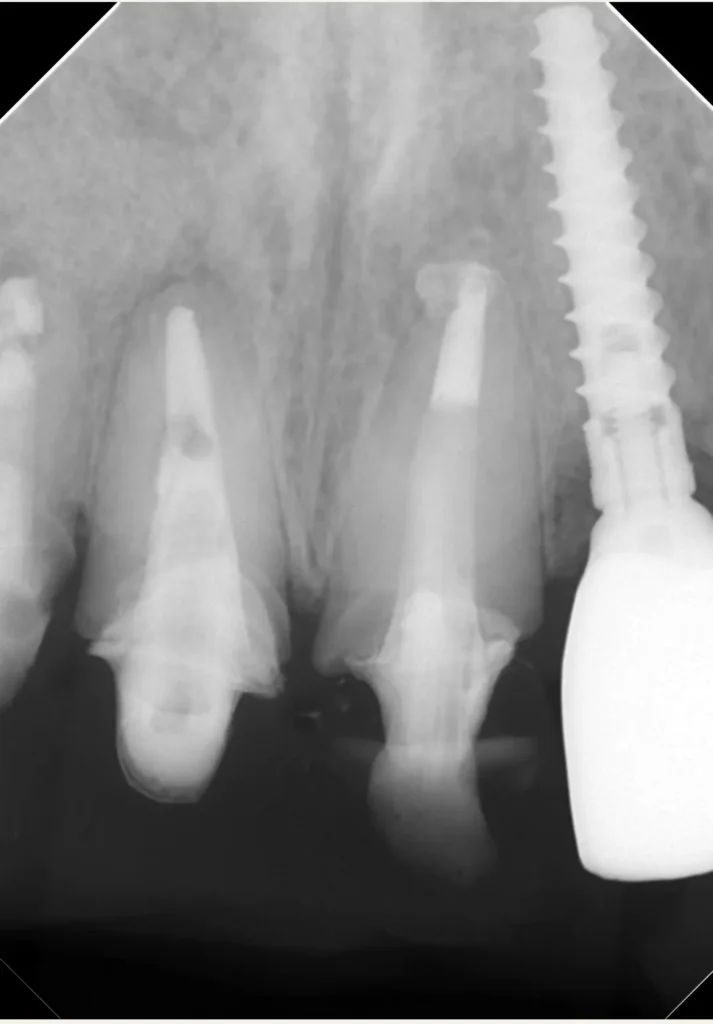

自費根管治療症例6 治療前(外科的歯内療法)

「前歯がなんとなく違和感がある」

初診時レントゲン写真

インプラント隣の歯の根の先に人工材料が逸出しています。

初診時レントゲン写真2

右側(向かって左)の歯は以前、他院で外科的歯内療法を受けています

術中レントゲン写真

右側1番(真ん中)の歯は歯根破折のため抜歯になりました(コツ補填材を抜歯窩に充填)

2本とも歯根端切除術を行いました